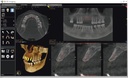

Introducing the CS 9300 Premium Panoramic, Cephalometric, and Cone Beam System from Carestream Dental – your ultimate solution for top-quality dental imaging. This state-of-the-art machine offers both 2D panoramic and cephalometric dental X-rays, as well as adjustable 3D cone beam images in up to seven different field of view sizes, extending up to 17x13.5 cm. This comprehensive range of imaging capabilities makes it a versatile tool, perfect for supporting a wide array of dental, surgical, or orthodontic examinations.

With the CS 9300 Premium, you can expect unparalleled image clarity and precision, allowing you to confidently diagnose and plan treatments with ease. Whether you're performing routine dental check-ups, complex surgical procedures, or orthodontic assessments, this system ensures outstanding results.

The CS 9300 is a multimodality imaging system that offers a wide range of 2D and 3D imaging options.

2D imaging:

3D imaging:

The CS 9300's 2D panoramic x-ray imaging capabilities are powered by variable focal trough technology, which provides optimal clarity for every image. The system's 3D imaging capabilities are based on cone beam technology, which delivers high-resolution images with a low radiation dose.

The CS 9300 is a versatile imaging system that can be used for a wide range of dental applications, including:

The system's multimodality capabilities make it an ideal choice for dental practices that need a comprehensive imaging solution.